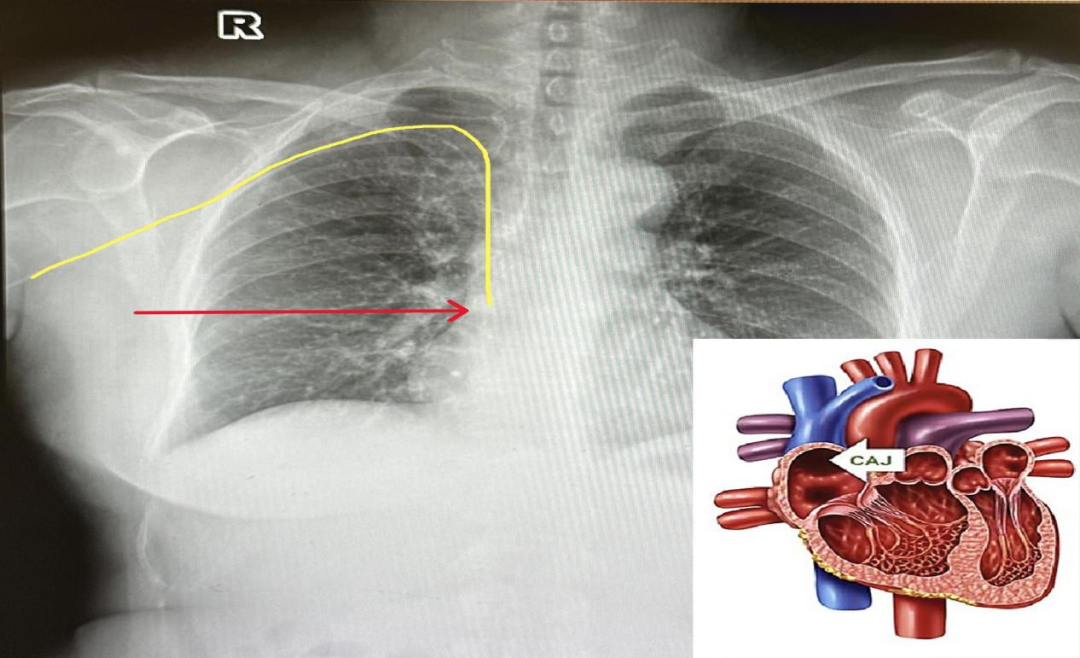

②智能定位,锁定“黄金位点”: 当导管尖端接近心脏的理想位置(上腔静脉与右心房交界处,CAJ点)时,系统能智能识别心电图(ECG)P波的特征性颜色变化,瞬间锁定最佳留置位置,确保导管尖端“一次到位”,精准无误!

在广州和谐医院肿瘤中心,静疗团队为他应用了最新的 3CG磁导航PICC技术。整个置管过程仅用了20余分钟,在磁导航的实时引导下,导管精准、顺畅地一次到位直达心脏CAJ点!术后胸片确认位置“完美”。黎叔终于有了一条可靠、安全的“生命通道”,可以安心接受后续治疗了。“又快又准,还没那么难受,心里踏实多了!”黎叔感慨道。